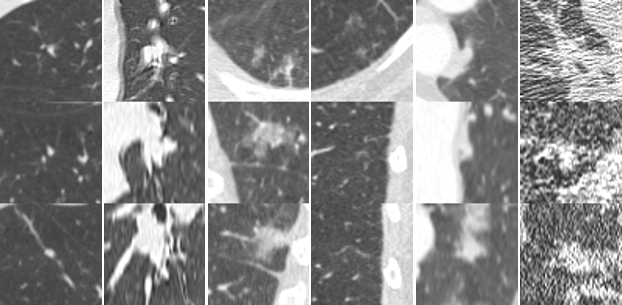

A summary of the observer study is shown in Table 4. Among 127 CAD marks, 108, 91, 69, and 41 CAD marks were accepted as nodules \geq 3 mm by at least 1, 2, 3, or 4 readers, respectively; 6 out of 19 remaining CAD marks were considered as nodule << 3 mm. Examples of nodules found in this observer study are shown in Figure 2(c). We shared the set of additional nodules on the LUNA16 website to be used for further development of CAD systems.

Refer to caption

(a) true positives with highest probability

(b) random true positives at 1 FP/scan

(c) false positives accepted as nodules by radiologists

(d) random false positives at 1 FP/scan

(e) false negatives from the candidate detectors

(f) random false negatives at 1 FP/scan

Figure 2: Examples of true positives, false positives, and false negatives from the combined system. Each lesion is located at the center of the 50×50505050\times 50 mm patch in axial, coronal, and sagittal views.

Examples of lesions detected or missed by the combined CAD system are shown in Figure 2. Nodules with a wide range of morphological characteristics are detected at 1 FP/scan, showing that ConvNets are capable of capturing morphological variation of nodules in the network. Larger nodules are unlikely to be missed, which is just as well as there is a strong positive correlation between size and malignancy risk. Most false positives are large vessels, scar tissue, spinal abnormalities, and other mediastinal structures. These false positives are a challenge. In scans from subjects with interstitial lung disease, there are, even in mild cases, regions with irregular opacities that can lead to a large number of erroneous nodule CAD marks. Other false positives are caused by motion artifacts and extreme noise. The false negatives were small and/or had irregular shapes. Improving the robustness of the candidate detection algorithms to detect small nodules should further improve the performance.